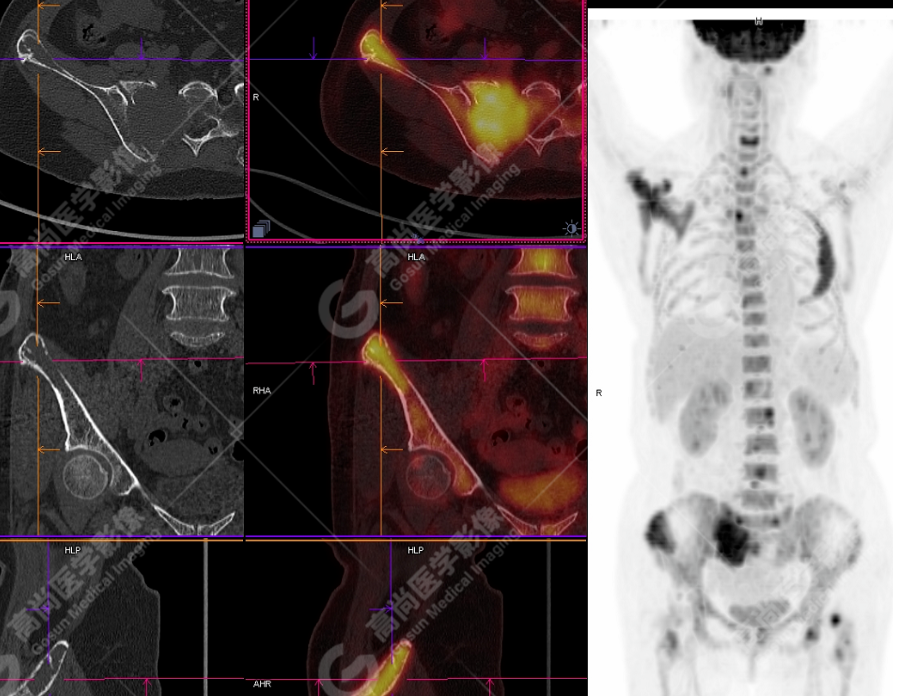

颅骨、寰椎前弓左侧份、第 6 颈椎、双侧肩胛骨(右侧为著)、左侧第 4 肋骨、第 1 胸椎、第 4 胸椎、第 2 腰椎及附件、第 4 腰椎及附件、骶骨、右侧髂骨、左侧坐骨结节、左侧股骨颈、双侧股骨小转子等均不同程度骨质吸收、破坏,其中右侧肩胛骨、左侧第 4 肋骨及骶骨右侧份软组织肿块影形成,上述病变均考虑恶性肿瘤(血液系统来源,多发骨髓瘤可能性大),建议右侧髂骨翼穿刺活检明确。

(4)PET-CT 影像表现:在溶骨性破坏区出现相重叠的 18F- FDG 高代谢区;通常呈弥漫性高代谢区。